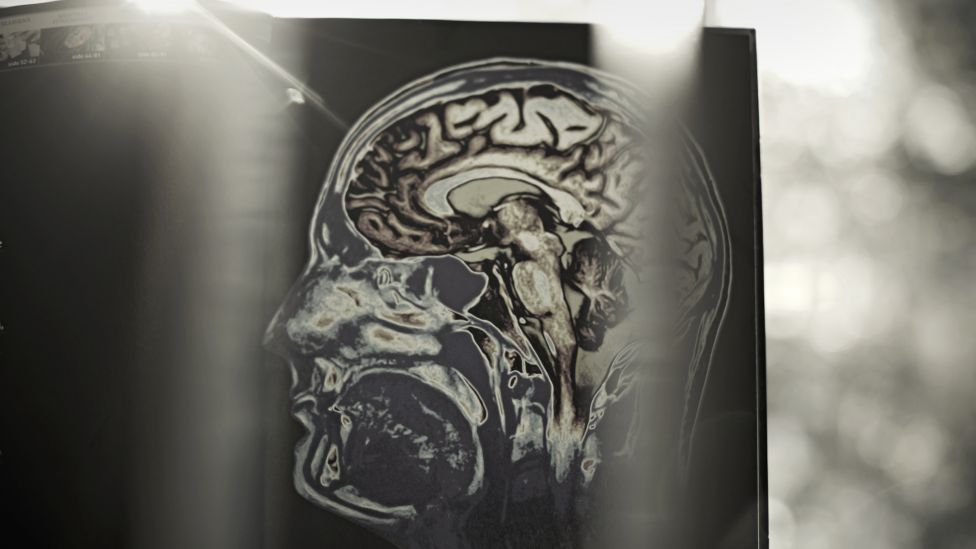

Egypterne så til hjertet og grekerne til kroppsvæsker. Vi ser til hjernen. Hjerneskanning har avdekket avvik hos psykisk syke. For eksempel er det trolig lavere aktivitet i hippocampus hos deprimerte. Det lille området innenfor tinningen, oppkalt etter sjøhesten på grunn av sin form, påvirker hukommelse og læring. Men det er delte meninger om hvordan dette skal tolkes. Oppstår lidelsene i hjernen, eller er det hjernen som reagerer på noe utenfor den selv?

– Det er på ingen måte så enkelt. Vi har 130 milliarder hjerneceller når vi blir født. Disse cellene sender signaler, og noen av dem har fem hundre tusen koblinger til andre celler. Det er det mest komplekse systemet vi kjenner, og umulig å forstå, forteller Espen Dietrichs, en av dem som forstår noe av det.

– Prinsippet er jo at alt kommer fra hjernen. Alt vi kaller psykiske problemer, går nettopp på signalene mellom hjernecellene. Så kan du si: Hva i hjernen er det som forårsaker det?

– Jeg tror det. Jeg tror ikke på noe utenom-hjerne-ting. Jeg tror det er forklarbar biologi, for å si det sånn. Vi vet jo at hjernen er det vi kaller plastisk, at den forandrer seg. Alt vi opplever, setter spor, og derfor har vi forskjellige hjerner. Vi reagerer forskjellig. Alt er med på å forme oss: kosthold, miljø, opplevelser. Dette gjør oss disponerte for psykiske svingninger, sier han.

– Alt er hjernebiologi, og depresjoner kommer også fra hjernen. Jeg tror jo på biologisk psykiatri, men hjernen er så komplisert at det er fryktelig mye vi ennå ikke forstår.